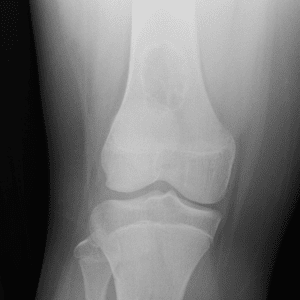

Pediatric Radiographs